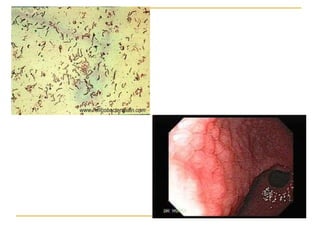

   Pruebas invasivas (requieren muestras gástricas): cultivo,

ureasa, histopatología, PCR y FISH.

6.-   Para el diagnóstico de infección por H. pylori durante la

endoscopia se recomienda la obtención de biopsias

gástricas (de antro y cuerpo) para histopatología.